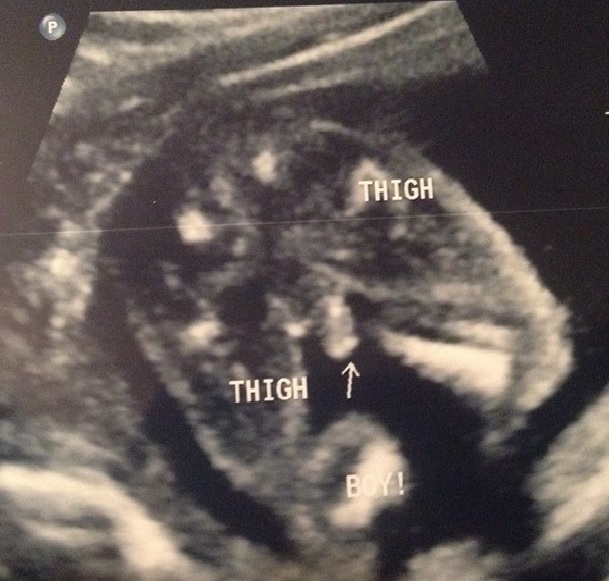

Had our anatomy scan today. Everything looked great except a white spot on baby boys heart. I freaked out and decided to get the verifi blood test to check for genetic abnormalities. Baby was 100% confirmed boy though. Here is the pic. He had no problem showing off his goodies!